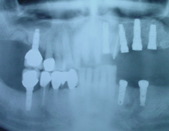

The term ‘Dental Implants’ refers to the surgical placement of artificial roots which help replace missing or badly damaged teeth. Other methods to replace missing teeth include dentures or bridges. The advantages of Implant tooth restoration is that it presents a more permanent solution.

The advent of Dental Implants removed the need to cut down adjacent teeth to restore a missing tooth. In most cases an implant can fill out the missing space and restore the esthetic look of the area with no collateral damage. The adjacent teeth can live happily ever after, instead of needing to support a missing tooth, they now can enjoy the support of the adjacent implant crown.

The placement of Implants involves a short surgical procedure, which requires placing a screw-like structure into the jaw bone. The Bone and Implant need to integrate, this takes about 3-4 months, the Implant Fixture and final Implant Crown can be fitted.